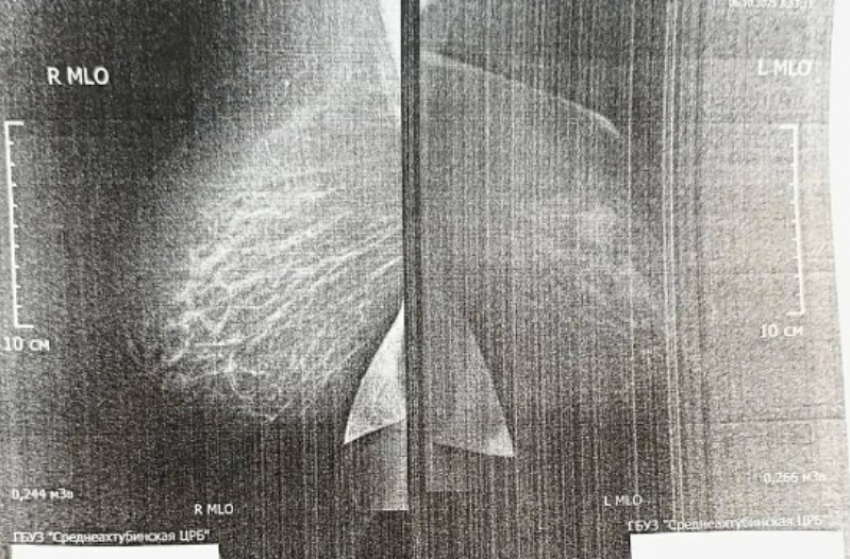

В ходе маммографии также было обнаружено образование в молочной железе. После консультации с онкологом диагноз подтвердился, и сейчас пациентка проходит предоперационное лечение в областном онкологическом диспансере, где ей оказывается вся необходимая высокотехнологичная помощь.